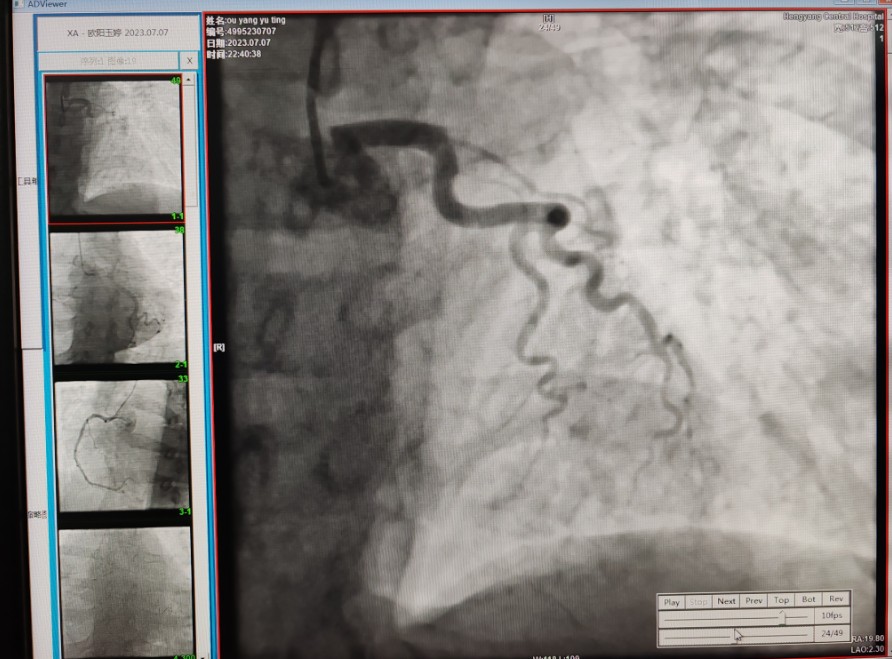

22:29分患者經(jīng)院內(nèi)綠色通道送達(dá)導(dǎo)管室,手術(shù)由雷剛副主任醫(yī)師主刀,楊繼賀副主任醫(yī)師為第一助手,介入技師及護(hù)士密切配合,聞訊而來的趙慶禧主任醫(yī)師坐鎮(zhèn)協(xié)調(diào)指揮。22:37分手術(shù)開始,冠脈造影顯示心臟上最重要的一條冠狀動脈-前降支開口齊頭閉塞,血管粗大且血栓高負(fù)荷,非??简?yàn)介入術(shù)者的手術(shù)能力,一旦發(fā)生冠脈無復(fù)流或操作不慎血栓帶入回旋支導(dǎo)致循環(huán)崩潰,病人幾乎無生還希望;此時,患者手術(shù)臺上仍持續(xù)胸痛,且血氧飽和度在高流量吸氧狀態(tài)下不到80%,雷剛副主任醫(yī)師一方面指揮鎮(zhèn)靜鎮(zhèn)痛及抗心衰治療,一方面緊急啟用IABP(主動脈球囊反搏),然后精細(xì)操控細(xì)如發(fā)絲的介入導(dǎo)絲迅速通過病變,并予冠脈球囊擴(kuò)張、冠脈內(nèi)溶栓、抗痙攣藥物使用、植入冠脈支架,最終成功開通“罪犯”血管,且無手術(shù)并發(fā)癥發(fā)生,整個過程張弛有度、快慢結(jié)合、一氣呵成?;颊咝g(shù)后胸痛明顯好轉(zhuǎn),血氧飽和度上升至96%,術(shù)后1天轉(zhuǎn)出監(jiān)護(hù)病房,第3天拔出IABP,目前已康復(fù)出院。